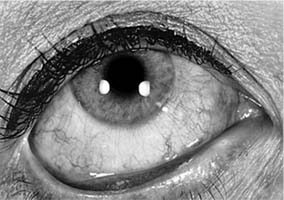

HAY FEVER CONJUNCTIVITIS (See Also Chapter 5.)

This disease is characterized by edema and hyperemia of the conjunctiva and lids (Figure 16-1) and by itching, which is always present, and watering of the eyes. There is often an associated itching sensation in the nose as well as rhinorrhea. The conjunctiva appears pale and boggy because of the intense edema, which is often rapid in onset. There is a distinct seasonal incidence, some patients being able to establish the onset of their symptoms at precisely the same time each year. These times usually correspond to the release of pollens by specific grasses, trees, or weeds.

Figure 16-1: Hay fever conjunctivitis. Note edema and hyperemia of the conjunctiva. (Courtesy of M Allansmith and B McClellan.)